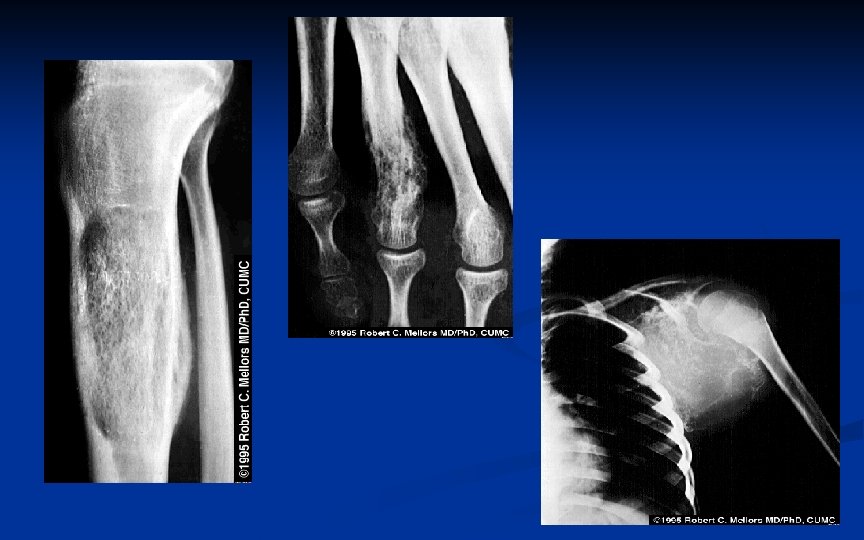

SARCOMA DE EWING 5 -15 anos (< 25 anos) Diáfises de ossos longos, principalmente Ms. Is (com extensão freqüente para a metáfise) e ossos chatos do ombro e pelve Como maioria dos sarcomas, leve predominância masculina: 2: 1

SARCOMA DE EWING RX Lesão destrutiva na diáfise de osso longo com reação periosteal em casca de cebola Início metáfise e rápido comprometimento diáfise (extensão) Metástases salteadas não são descritas Pode envolver todo o osso Nos ossos chatos, aparece como lesão destrutiva não específica

Neoplasia causando destruição intraóssea, irrompendo através da cortical e elevando o periósteo.